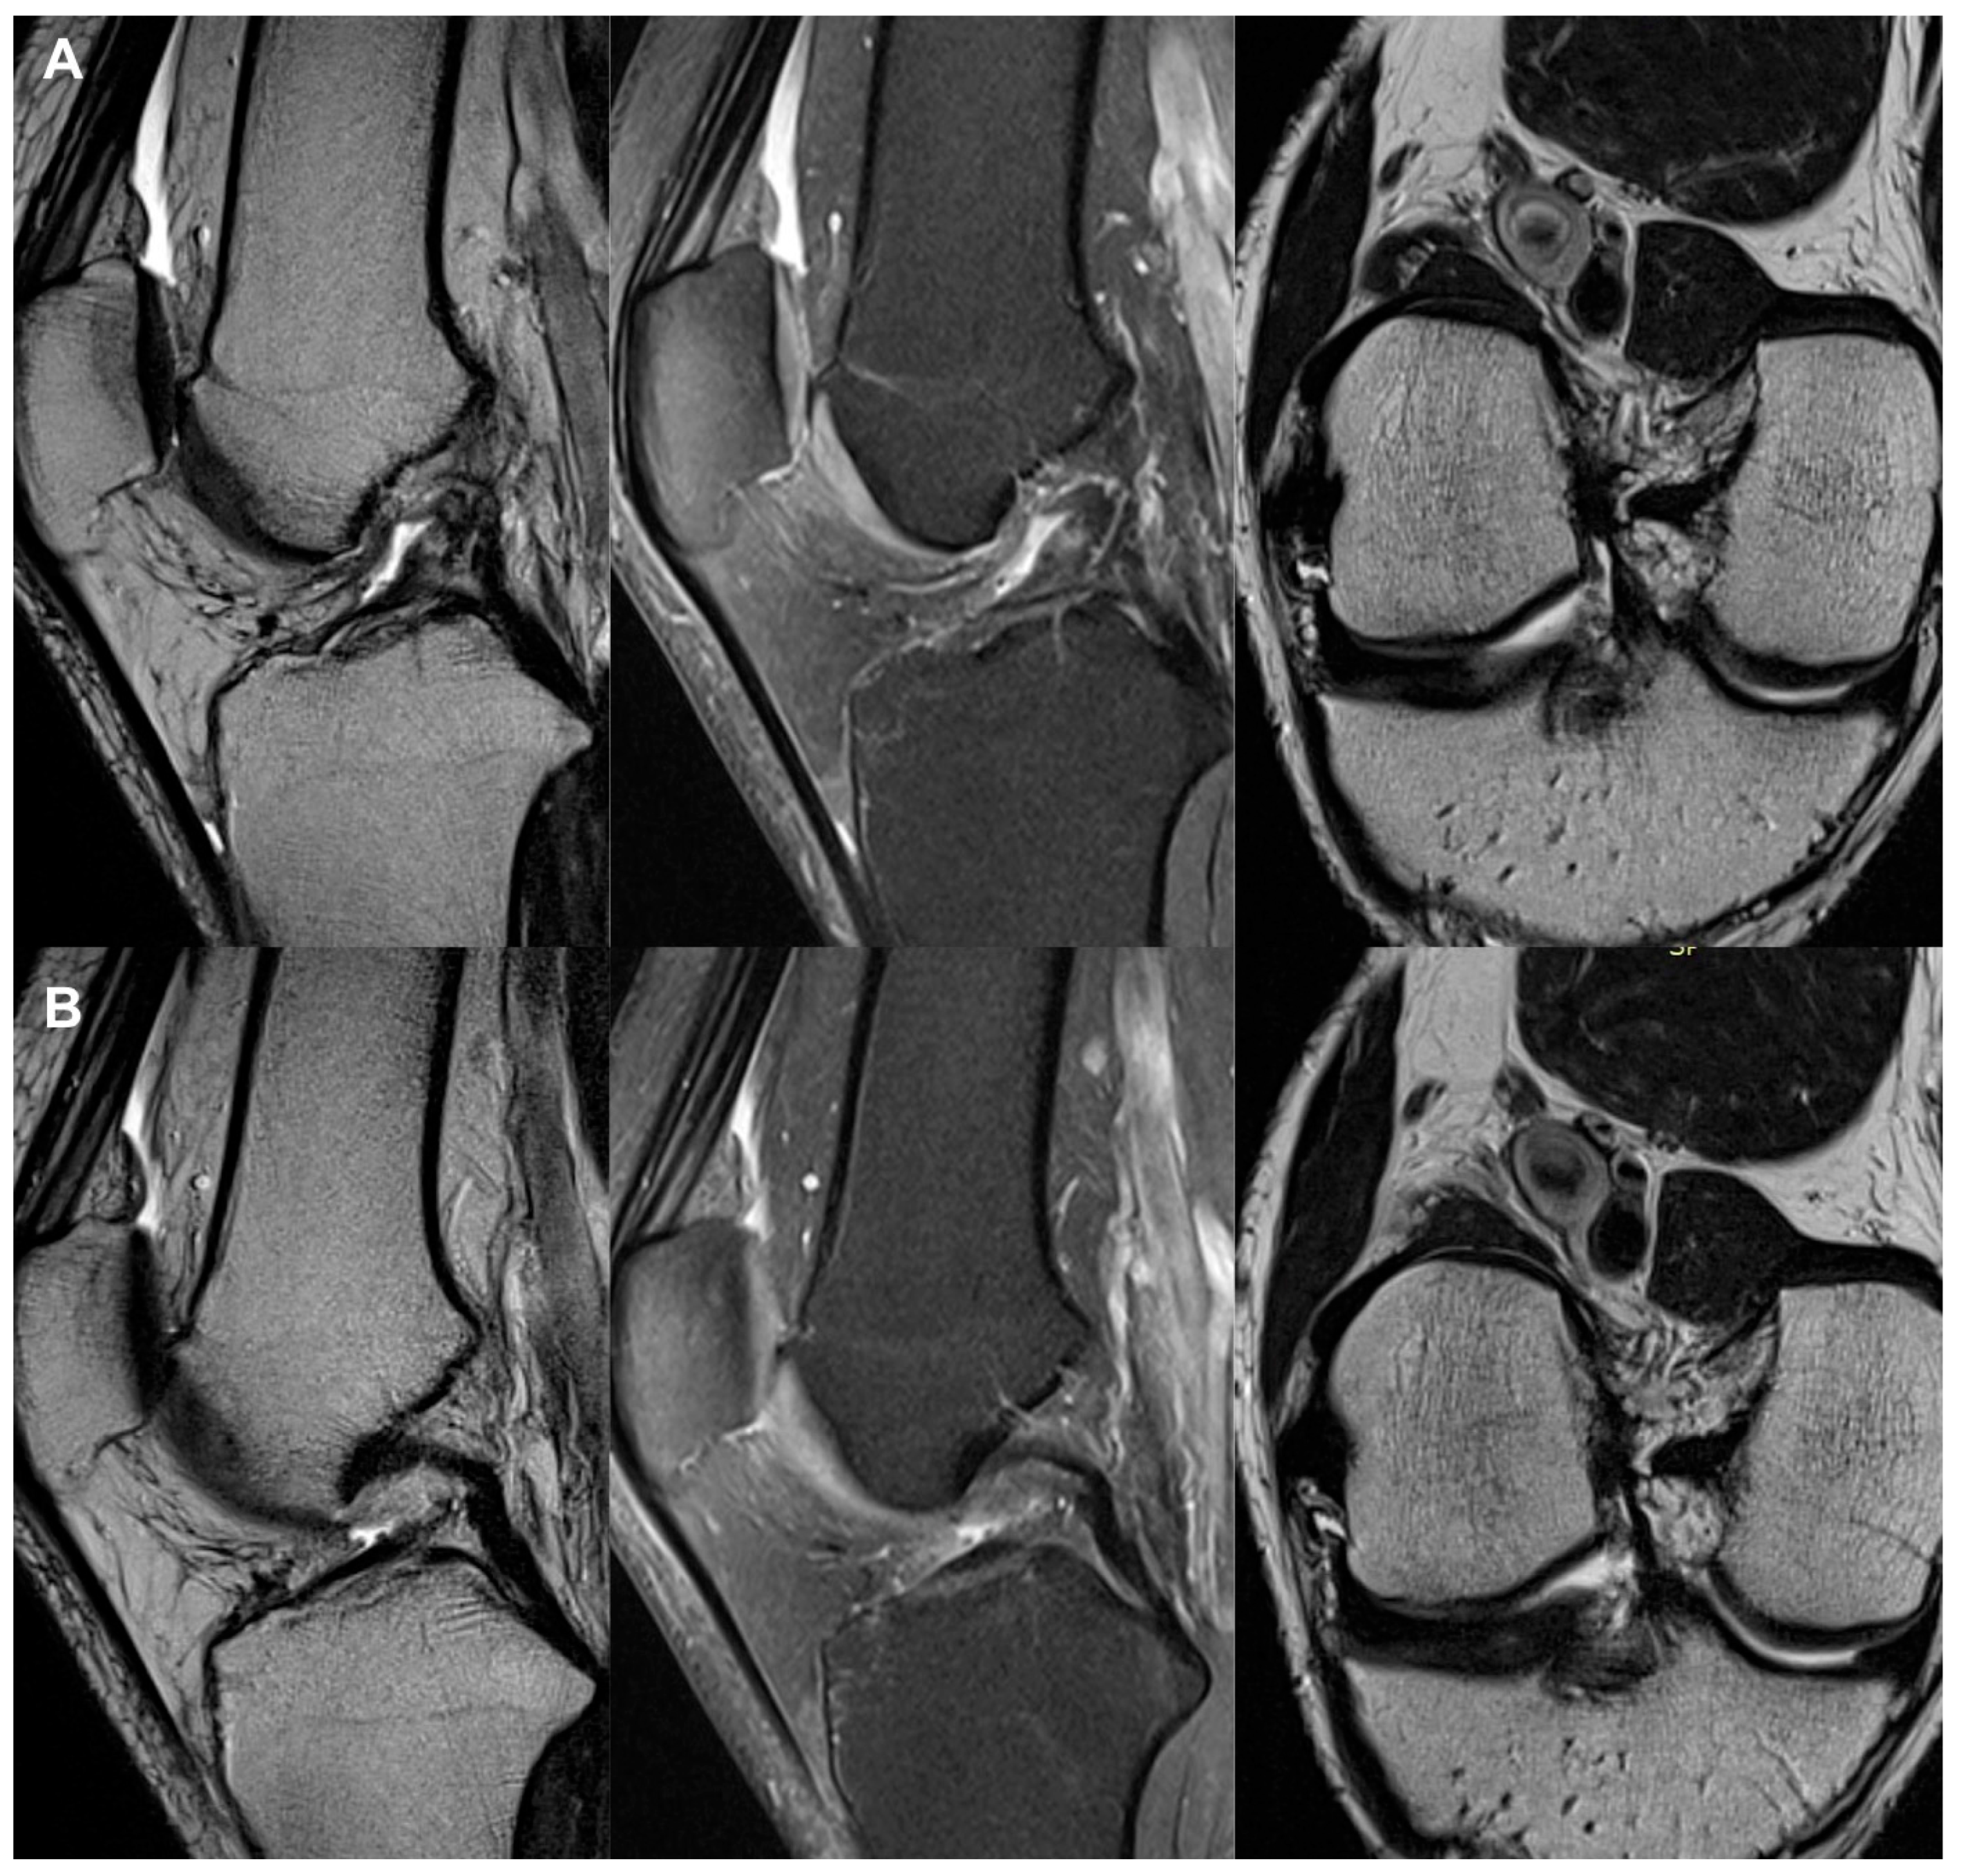

3.3. Imaging Analysis